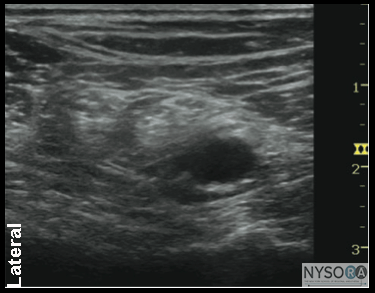

General Considerations Performance of a sciatic block above the popliteal fossa benefits from ultrasound guidance in several ways. The anatomy of the sciatic nerve as it approaches the popliteal fossa can be variable, and the division into the tibial nerve (TN) and common peroneal nerve (CPN) occurs at a variable distance from the crease. Knowledge of the location of the TPN and CPN in relation to each other is beneficial in ensuring the anesthesia of both divisions of the sciatic nerve. Moreover, with nerve stimulator-based techniques, larger volumes (e.g., >40 mL) of local anesthetic often are required to increase the chance of block success and rapid onset. A reduction in local anesthetic volume can be achieved with ultrasound guidance because the injection can be halted once adequate spread is documented. The two approaches to the popliteal sciatic block common in our practice are the lateral approach with patient in supine (more commonly, oblique position) and the posterior approach (Figure 2). It should be noted that with the lateral approach, the resulting ultrasound image is identical to the image in the posterior approach. Both are discussed in this chapter. Only the patient position and needle path differ between the two approaches; the rest of the technique details are essentially the same. Ultrasound Anatomy With the posterior and the lateral approaches, the transducer position is identical; thus the sonographic anatomy appears the same. However, note that although the image appears the same, there is a 180° difference in patient orientation. Beginning with the transducer in the transverse position at the popliteal crease, the popliteal artery is identified, aided with the color Doppler ultrasound when necessary, at a depth of approximately 3 to 4 cm. The popliteal vein accompanies the artery. On either side of the artery are the biceps femoris muscles (lateral) and the semimembranosus and semitendinosus muscles (medial). Superficial (i.e., toward the skin surface) and lateral to the artery is the tibial nerve, seen as a hyperechoic, oval, or round structure with a stippled or honeycomb pattern on the interior (Figure 3A and B). If difficulty in identifying the nerve is encountered, the patient can be asked to dorsiflex and plantar flex the ankle, which makes the nerve rotate or move in relation to its surroundings. Once the tibial nerve is identified, an attempt can be made to visualize the common peroneal nerve, which is located even more superficial and lateral to the tibial nerve. The transducer should be slid proximally until the tibial and peroneal nerves are visualized coming together to form the sciatic nerve before its division. (Figure 4A and B). This junction usually occurs at a distance between 5 and 10 cm from the popliteal crease but this may occur very close to the crease or (less commonly) more proximally in the thigh. As the transducer is moved proximally, the popliteal vessels move anteriorly (i.e., deeper) and therefore become less visible. Adjustments in depth, gain, and direction of the ultrasound beam should be made to keep the nerve visible at all times. The sciatic nerve typically is visualized at a depth of 2 to 4 cm.